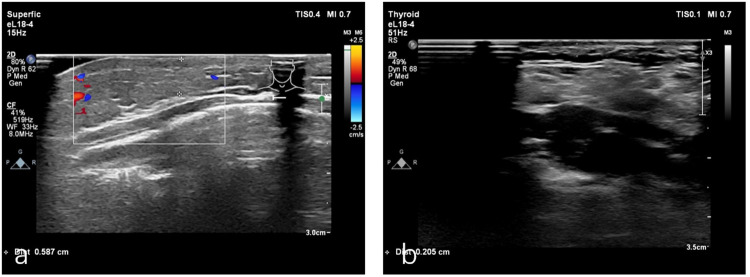

Kaposiform hemangioendothelioma(KHE) without Kasabach-Merritt phenomenon is a rare tumor primarily observed in pediatric patients; however, its documentation in the literature remains limited. We reported about a 1-year-old boy diagnosed with superficial KHE who received oral propranolol in combination with topical sirolimus and reviewed relevant reports and treatment of superficial KHE.